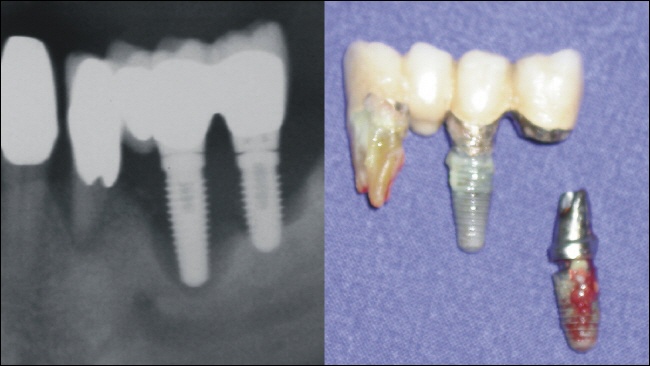

1. Fortgeschrittene Entzündung um das Implantat mit dadurch bedingtem Knochenabbau.

Fehlende Nachkontrolle über Jahre hinweg, sowie eine schlechte Mundhygiene können dazu führen, dass sich für den Patienten vollkommen unbemerkt eine fortgeschrittene Entzündung durch mikrobielle Beläge um das Implantat herum ausbreitet. Der Implantologe spricht von einer sogenannten Periimplantitis (Peri = um-/herum, implantat=künstliche Zahnwurzel, -itis=Entzündung). Eine Entkeimung der Implantatoberfäche ist im fortgeschrittenen Stadium, ähnlich wie bei der fortgeschrittenen Parodontitis (=Parodontose), leider wenig erfolgsversprechend.

Ein Bruch des Implantats ist immer die Folge einer mechanischen Überbelastung. Bei den etablierten rotationssymmetrischen Implantaten gehören Brucherscheinungen des Implantats jedoch der Vergangenheit an. Die sogenannten durchmesserreduzierten Implantate sind zwar aufgrund ihres geringen Durchmessers weniger bruchstabil, in bestimmten Situationen, wie beispielsweise zum Ersatz unterer Frontzähne oder oberer seitlicher Frontzähne, jedoch die einzige Möglichkeit. Bei einer fachgerechten Auswahl und Versorgung zeigen auch die durchmesserreduzierten Implantate kein erhöhtes Risiko für Frakturen (Brüche). Bei den heute nicht mehr üblichen Blattimplantaten, wie auch bei den nicht zu empfehlenden Diskimplantaten, waren/sind Brucherscheinungen keine Seltenheit. Der große Nachteil hierbei ist, dass die zwangläufige Entfernung des gebrochenen Implantats oftmals einen erheblichen Knochendefekt hinterlässt.